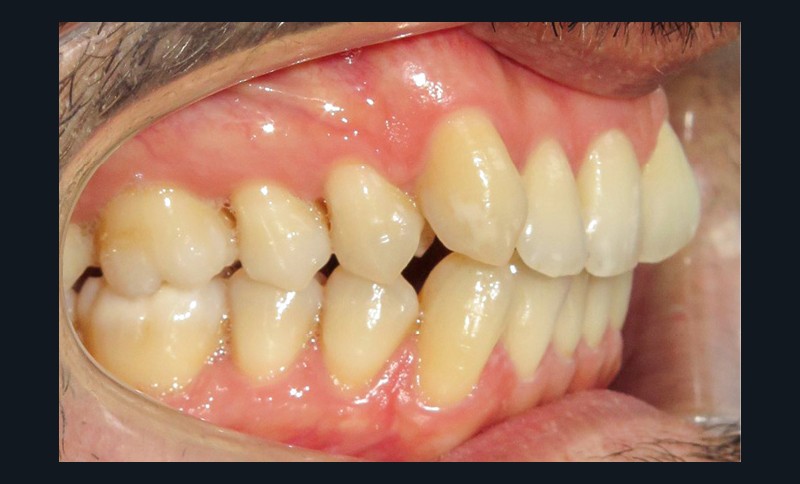

Diagnostic (fig. 1a-i)

Le patient consulte initialement pour des défauts d’alignement. L’examen clinique confirme l’existence d’un encombrement antérieur bimaxillaire, mais révèle aussi la présence d’une Classe II dentaire sévère, d’une exoclusion de la 27 et de troubles parodontaux (peu ou absence de papilles inter-dentaires). Sur le plan squelettique, le patient est relativement équilibré avec un profil harmonieux.